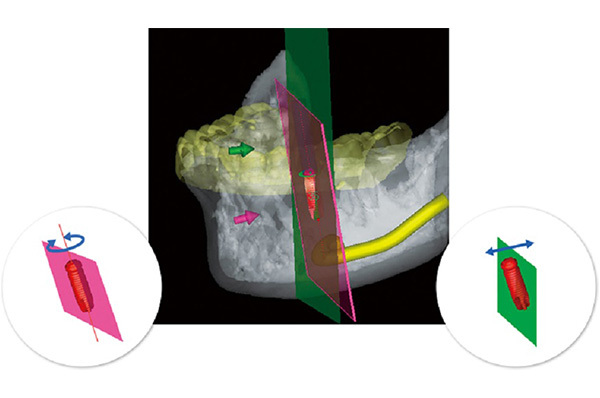

難症例でもインプラント治療を成功させるために、当院では最新のインプラントシュミレーションソフトiCATを用いてより精密な分析を行っています。

撮影させて頂いたCTを当院が導入している分析ソフトiCATを用いて、CTで得られた情報を3D化します。

構成された仮想空間にインプラントを仮置きして、シミュレーションすることによって、どの位置にインプラントを埋入すれば最適なのかを判断出来ます。

難症例でもインプラント治療を成功させるために当院では最新のインプラントシュミレーションソフトicatを用いてより精密な分析を行っています。

世界ではじめてicatシステムが可能にした「インプラント断面」により精度の高いインプラントシミュレーションを実現